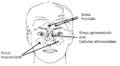

الاتصالات

يتصل جوف الأنف مع الوسط الخارجي في الأمام عبر المنخر ويتصل مع البلعوم الأنفي في الخلف عبر فتحة بيضية الشكل تدعى المنعر. كما يتصل جوف الأنف مع الجيوب جانب الأنفية عبر فتحات خاصة، ويسمح وجود هذه الفتحات بتفريغ محتويات الجيوب ومنع تراكمها. تفتح القناة الأنفية الدمعية التي تنقل الدمع على الصماخ الأنفي السفلي.[1][6][8] يفتح على جوف الأنف في الجمجمة الجافة (أي بعد إزالة المخطيات) بالإضافة لما سبق كل من الثقبة الوتدية الحنكية والنفق القاطعي والصفيحة المصفوية.[1]